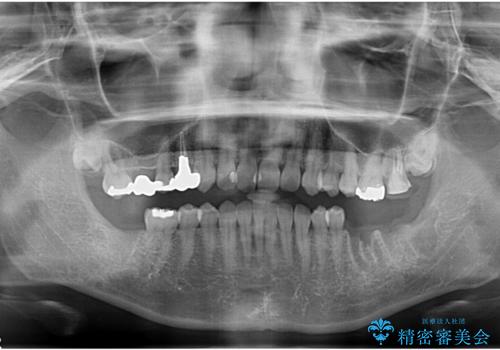

合計3本の奥歯を抜歯したところに、インプラント治療を行っています。

また、左上奥歯の根の治療および右下の虫歯治療も併せて行っています。

- 199.1万円 内訳:右下7、左下67(ストローマンインプラント 22万円×3本 チタンカスタムアバットメント 11万円×3本 ジルコニアクラウン11万円×3本 インプラント用仮歯 2.2万円×3本 骨増生 5.5万円×2ヶ所) 左上67(精密根管再治療 14.3万円×1本、仮歯1.1万円x2本、ジルコニアクラウン11万円×2本)右下6(セラミックインレー 7.7万円)プレミアムナイトガード 3.3万円費用は治療当時の料金となります